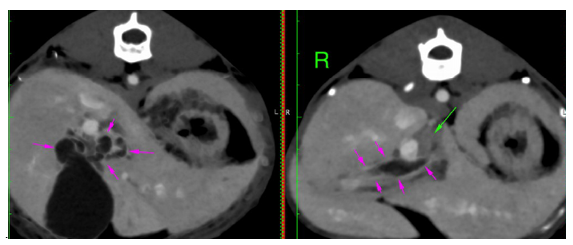

An ultrasonographic re-examination performed at 4 weeks showed a decrease in the intrahepatic bile duct size, however, transversal intraluminal septae at the level of the intrahepatic biliary tree were noted (Figure 5-white arrow). Portal flow velocity was recorded within normal limits, with regular flow (Figure 6).

Figure 5 1-month follow-up ultrasound scan. Transverse image of the intrahepatic biliary tree. Septal formation (white arrow) was seen bridging the walls of the hyperechoic duct. Echogenic to hyperechoic bile was seen at the level of the left and central liver.

Figure 6 Transverse image of the portal flow velocity (20 cm/s). Normal portal vein wave was present.